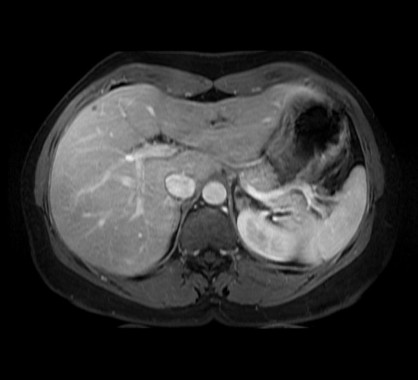

Pseudo kyste surrénalien

Case courtesy of Radiopaedia.org. From the case Adrenal pseudocyst